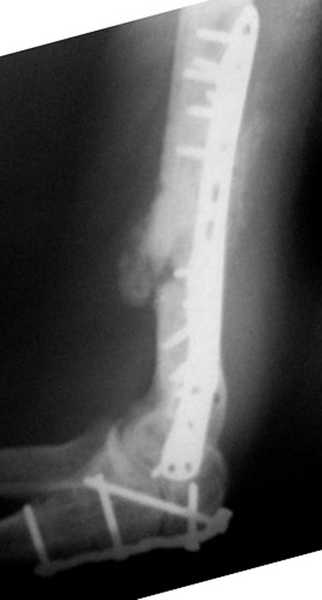

На примере два случая, извиняюсь за качество снимков, снимки и случаи из бывшего союза.

Первая больная с "успехом" была прооперирована 6 раз различными методами открытого и закрытого

остеосинтеза, включая то, что в Кисловодске заезжим австралийским "кудесником" на ложный сустав уложена скорлупа от страусиновых яиц. Последняя операция одиноким локинг плейт в одной из клиник.

Через год по поводу тех же проблем сделали ревизию, оригинальную пластину оставили как есть, только укрепили добавлением еще одной пластины и сделали костную пластику.

Через два месяца увидели признаки консолидации.